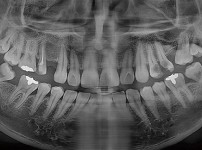

숙면임플란트 3개 - 스트라우만임플란트 (이*웅님)